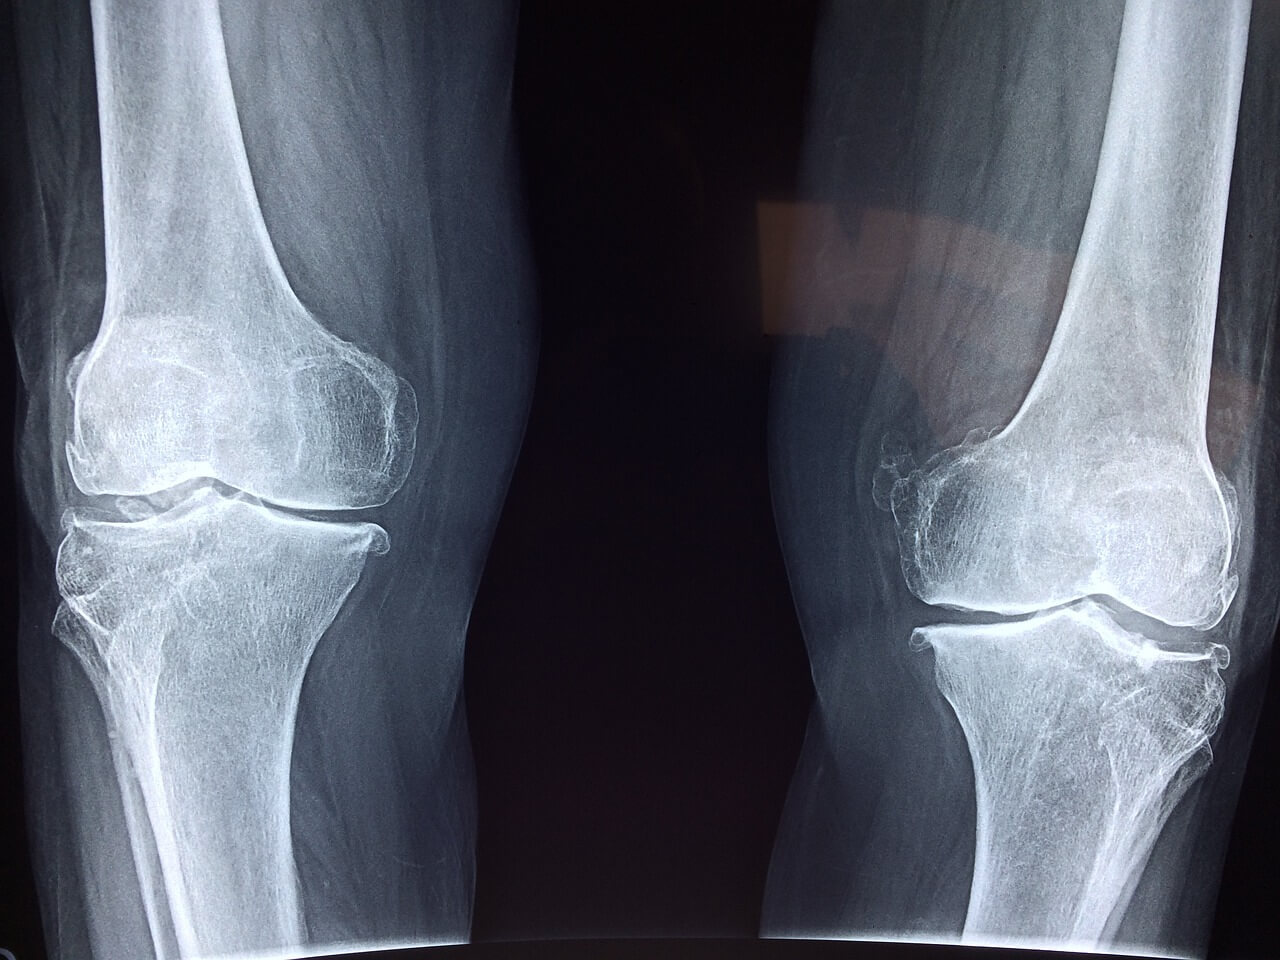

슬개골 연골 연화증 (chondromalacia of the patella) 원인 증상 및 치료법

슬개골 연골 연화증 (chondromalacia of the patella)이란 질병은 우리 일상 활동에 여러 불편함과 행동 범위에 제약을 유발할 수 있는 보통적으로 발생하는 무릎 질병입니다. 이런 상태는 슬개골 내부의 연골에 약간 손상되거나 노화 및 많은 쓰임으로 부드러워질 때 발생합니다. 오늘 이 곳에서는 슬개골의 연골 연화증 세계를 탐구해보고 발생하는 원인과 나타나는 증상을 이해하며 여러 효과적인 치료법을 공유합니다. 해당 질병에 대한 인식과 간단한 지식을 높임으로써 개인 또는 주변 지인이 무릎 장애의 증상을 효과적으로 관리하고 회복 및 완화할 수 있는 능력을 얻어 갈 수 있습니다.